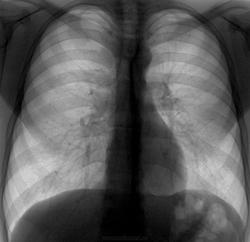

Флюорография. Молодой человек, жалобы на боль в грудной клетке, тудно дышать. Я уже написал норму.

Я вижу Правосторонний пристеночный пневмоторакс.Пациента отыскать и к хирургу.

Мышцы дают немного другую тень,а тут я вижу полоску газа пристеночно.

Правосторонний пневмоторакс +1. Сразу бросается в глаза еще и усиление легочного рисунка справа в нижних отделах, помимо полосы

А я еще сделал флгр на вдохе-выдохе, а вдруг проявится лучше. Ведь отправлять к торакальщикам, нужно более доказательный снимок. И вот что получилось на выдохе. Женщинам респект. Но, конечно, я не правильно закрутил интригу. Т.е. совсем не создал.

Я не увидел  признаков пневмоторакса, даже при повторном просмотре  после снимка на выдохе ( может мониторы разные, може глаза в "тяпницу").

Пневмоторакс справа отлично видно!

На первом снимке при первичном просмотре ПТ не увидел, только при повторном разглядывании. На втором снимке пневмоторакс виден лучше. Про спонтанные: все спонтанные ПТ, поступающие в наш госпиталь, были нетуберкулезной этиологии.